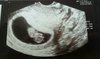

SuperHej ja po wizycie[emoji4]wszystko w jak najlepszym porządku.dzidzia ma 27 mm.następna wizyta 27.08 na 10.30[emoji4]Zobacz załącznik 888742

Ale śliczne maleństwo. Niech zdrowo rośnie.Hej ja po wizycie[emoji4]wszystko w jak najlepszym porządku.dzidzia ma 27 mm.następna wizyta 27.08 na 10.30[emoji4]Zobacz załącznik 888742

Piękna dzidzia gratulujęHej ja po wizycie[emoji4]wszystko w jak najlepszym porządku.dzidzia ma 27 mm.następna wizyta 27.08 na 10.30[emoji4]Zobacz załącznik 888742